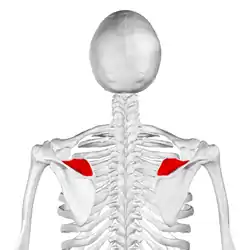

Left scapula. Dorsal surface. Supraspinatous fossa shown in red. | |

Left scapula. Dorsal surface. Supraspinatous fossa shown in red. | |

The human scapula Supraspinous fossa shown in red.

Supraspinous fossa shown in red. Supraspinous fossa shown in red.

Supraspinous fossa shown in red.